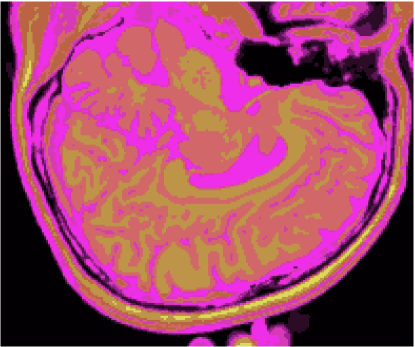

As figuras 2 (banda 0), 3 (banda 1) e 4 (banda 2) mostram a fatia 97 de um volume de imagens sagitais com 181 fatias e 0% de ruído, ponderadas em PD (densidade de próton), T1subscript𝑇1T_{1} e T2subscript𝑇2T_{2}, enquanto a figura 5 ilustra a composição colorida R0-G1-B2 da mesma fatia. Pode-se notar no topo do crânio, na parte inferior das imagens, a presença de artefatos, que podem ser resultantes de erros no simulador, mas que não são prejudiciais à análise, uma vez que, neste trabalho, não é dada ênfase à análise anatômica.

Figura 2: Imagem de RM da fatia 97 ponderada em PD

Figura 3: Imagem de RM da fatia 97 ponderada em T1subscript𝑇1T_{1}

Figura 4: Imagem de RM da fatia 97 ponderada em T2subscript𝑇2T_{2}

Figura 5: Composição colorida R0-G1-B2 das imagens da fatia 97 ponderadas em PD, T1subscript𝑇1T_{1} e T2subscript𝑇2T_{2}

3.1 Classificadores Dialéticos Objetivos

A figura 6 mostra os resultados de classificação, enquanto a figura 7 exibe os resultados de quantização para a imagem sem ruído da fatia 97, figura 5, usando os métodos KO, CM, KM, ODC-PME e ODC-CAN. Esses resultados ilustram qualitativamente as diferenças entre os métodos de classificação e quantização, dado que a fatia 97 possui todas as 13 classes presentes na análise [51].

Figura 6: Composição colorida R0-G1-B2 das imagens da fatia 97 ponderadas em PD, T1subscript𝑇1T_{1} e T2subscript𝑇2T_{2} (a) e resultados de classificação usando os métodos KO (b), CM (c), KM (d), ODC-PME (e) e ODC-CAN (f)